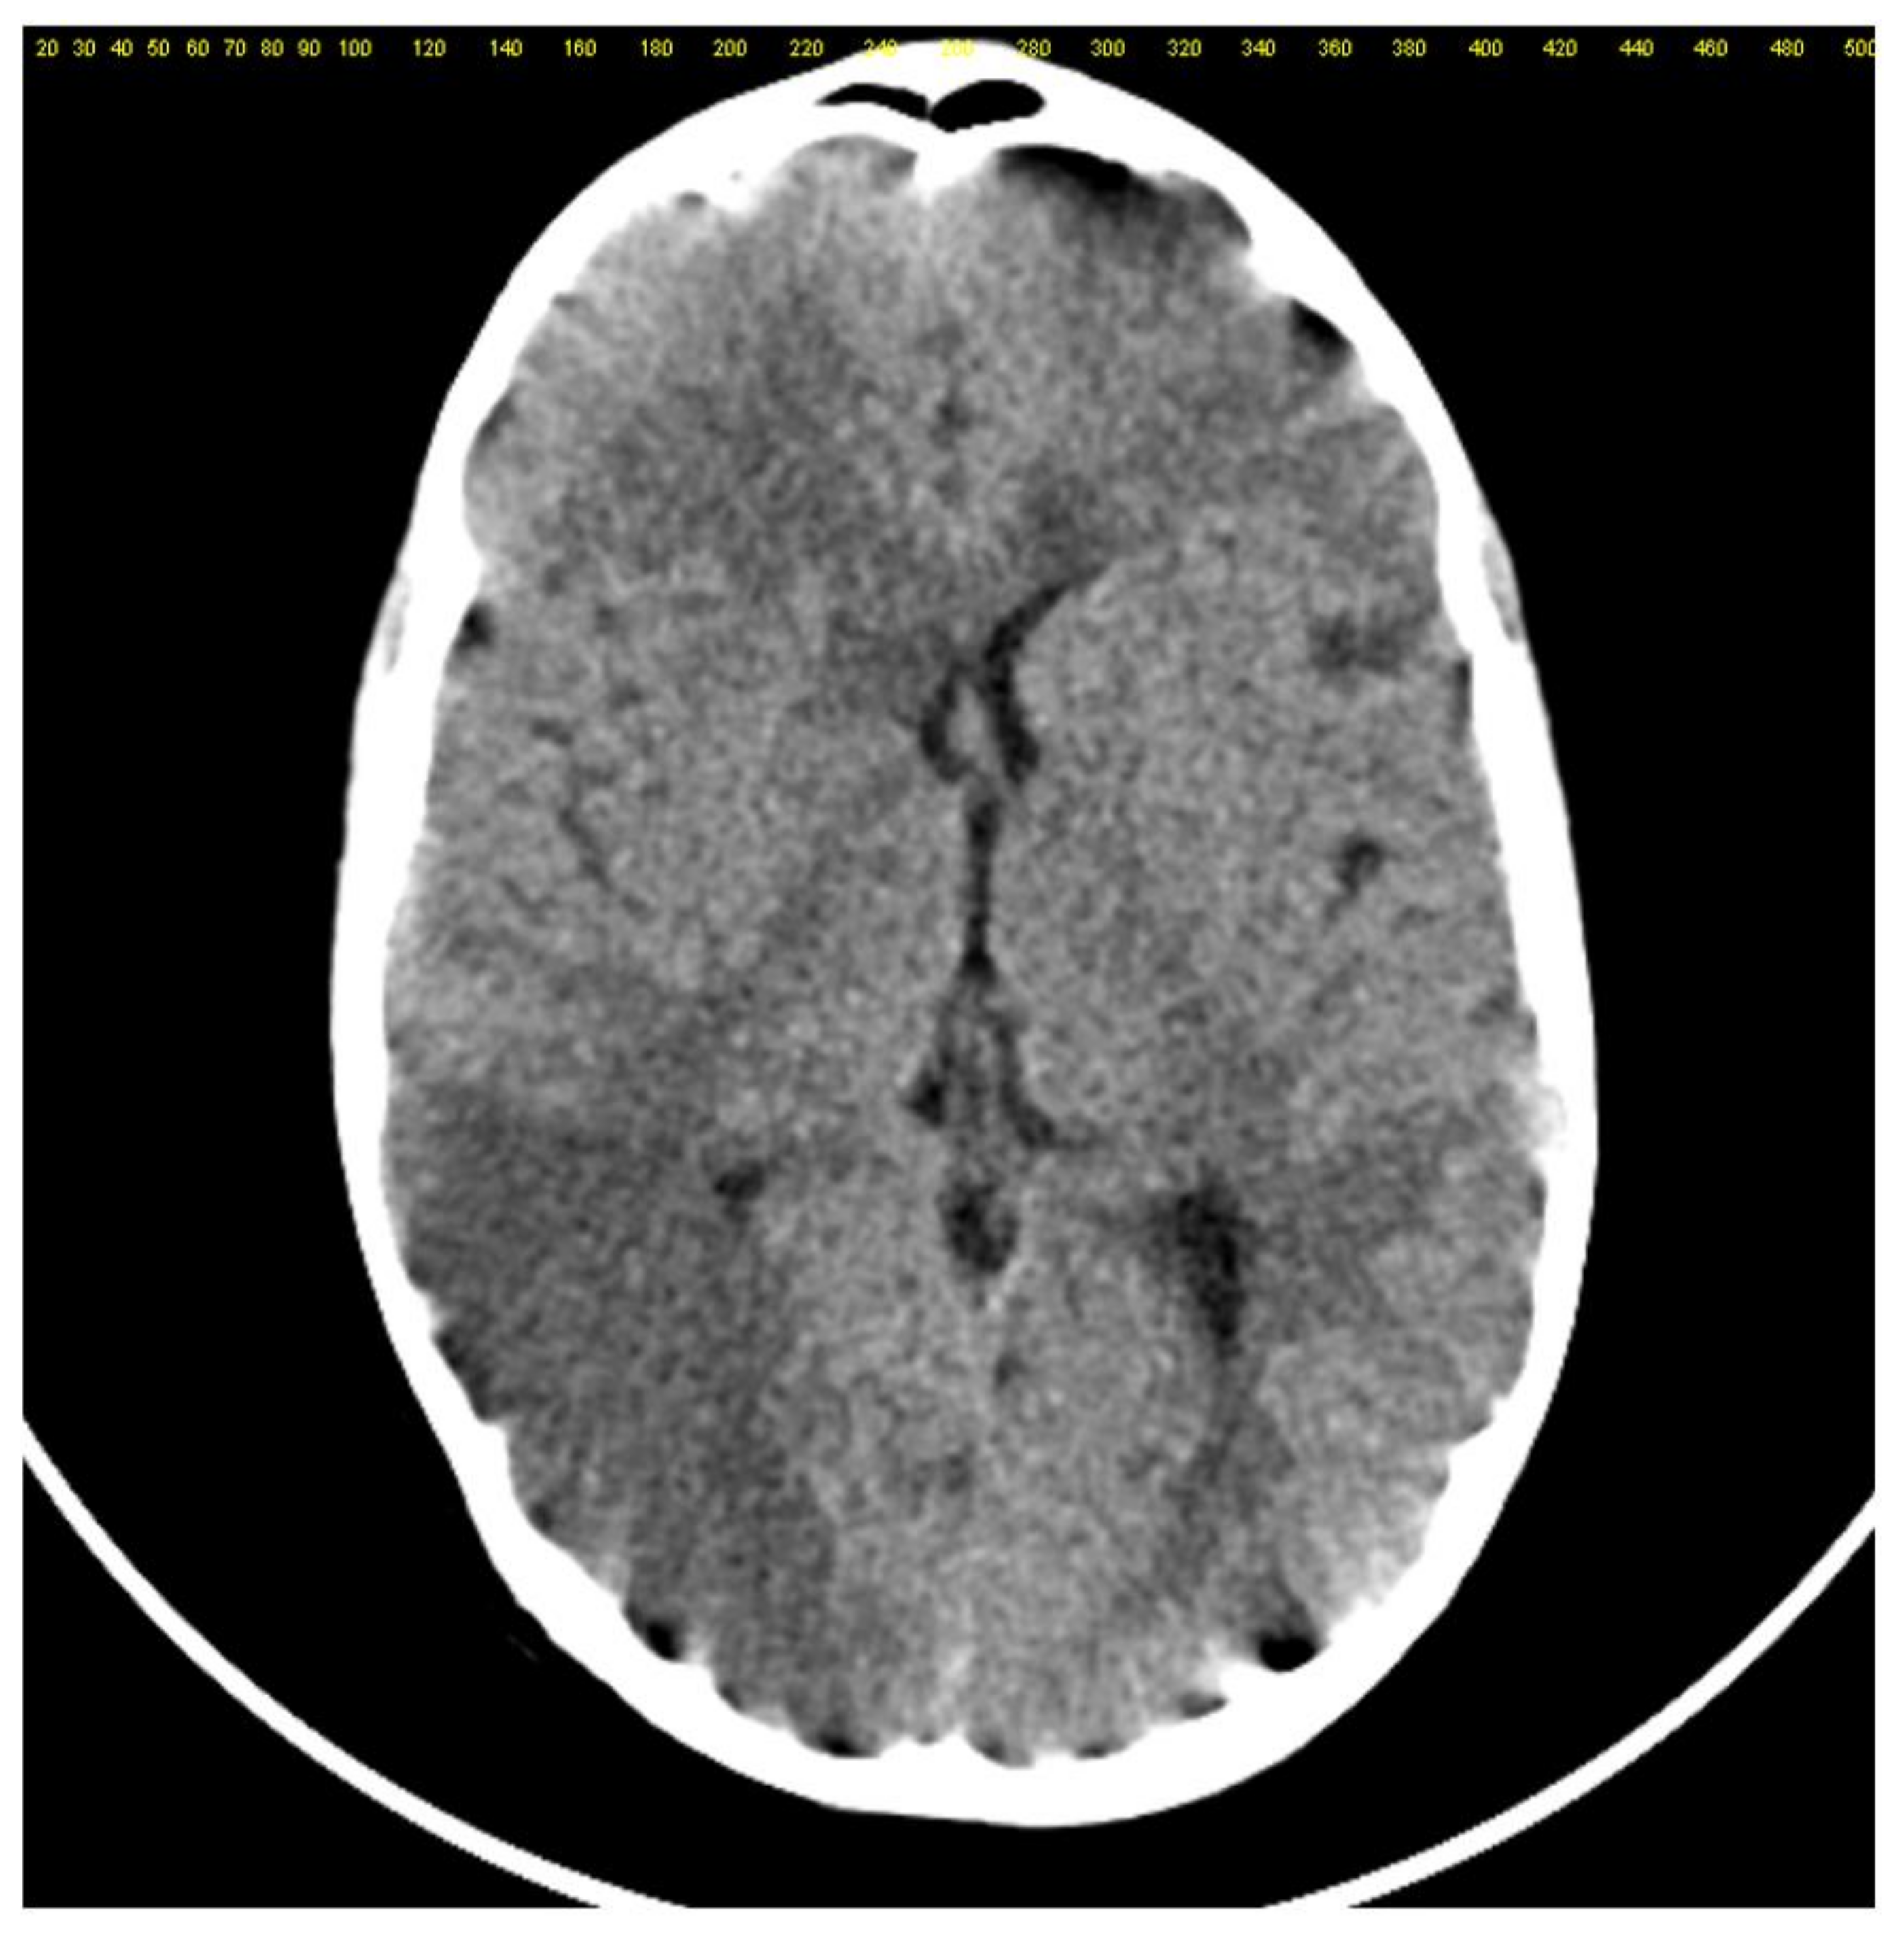

2. Case Report